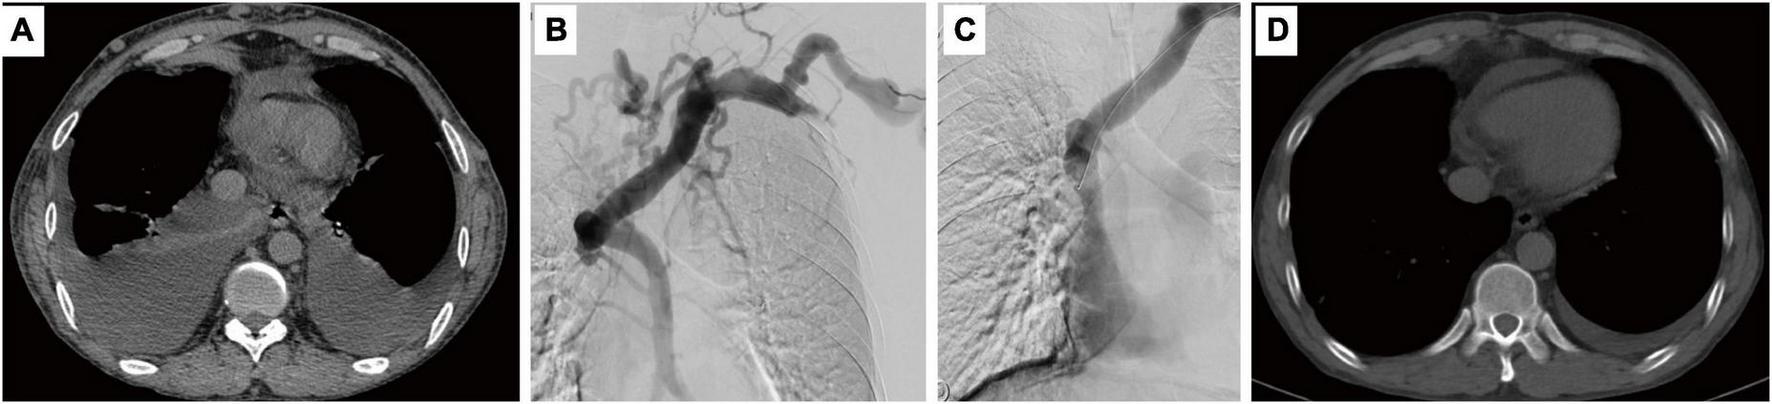

FIGURE 1

Computed tomography shows pleural effusion (A) and angiography shows superior vena cava occlusion (B). Balloon dilatation was performed (C) and pleural effusion no longer appeared after 4 months (D).

A 50-year-old man sought treatment in several hospitals because of a severe dry cough. The cough first appeared in December 2020 without obvious inducement, accompanied by a small amount of white foam sputum and sticky sputum. During 1 month, the patient’s cough gradually worsened, with dyspnea after activities and paroxysmal dyspnea at night. Cough symptoms were associated with postural changes, such as standing up from sitting, bending over, or turning over during sleep, which could trigger severe coughs, and the patient even had transient amaurosis (self-reported syncope three times). The patient was hospitalized at Xinqiao Hospital of Army Military Medical University (Chongqing, China) on 11 January 2021, and discharged on 21 January 2021. Computed tomography (CT) of the chest showed bilateral pleural effusion (Figure 1A), which was later tested to be chylous fluid (Table 1). The cough was relieved after extracting the pleural fluid. However, the relief could only last for 1 day until the pleural effusion reappeared. The patient had to have pleural effusion extracted every other day to relieve his cough, and the amount of pleural effusion was very large (800–1,000 mL each time). It was suspected that the severe cough was related to recurrent pleural effusion. To determine the cause of such a serious pleural effusion, the patient received enhanced CT, which found an occlusion in the superior vena cava. Because the patient had a long history of dialysis because of uremia, he was recommended to go to the nephrology department to treat his superior vena cava occlusion.

On 24th February, percutaneous balloon dilatation was performed to recanalize the superior vena cava (Figure 1C). The superior vena cava was clearly visualized and unobstructed. The collateral circulation mostly disappeared, and the stenosis was relieved.

Follow-up was conducted after 4 months and 12 months. Chest CT showed no pleural effusion (Figure 1D). The patient reported that cough symptoms were eliminated. Based on the results, we can confirm that the obstruction of the superior vena cava caused the patient to develop recurrent chylothorax, and further stimulated severe postural change-related cough.